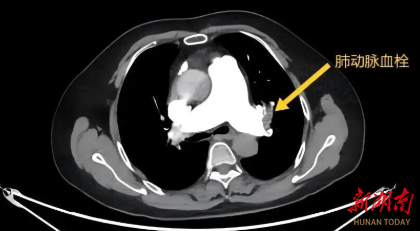

该院急诊医疗团队接诊后,立即为患者行CTA(CT血管造影)检查,最终确诊为急性肺栓塞——下肢深静脉血栓脱落后随血流阻塞肺动脉,导致心肺功能严重受损。情况危急,医疗团队果断采取溶栓治疗。经过数小时紧张救治,患者血栓逐渐溶解,血压回升,生命体征趋于稳定,最终转危为安。